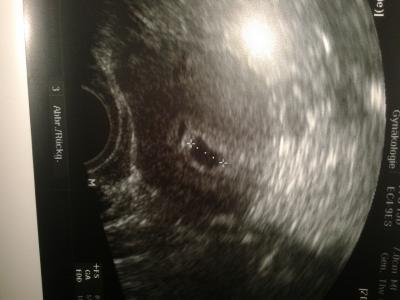

Hallo! Klar,immer her damit!So was schönes muss man doch teilen! Glückwunsch! Dann kann Weihnachten ja kommen! Uns ging es auch so! Endlich heute das erste US Bild u alles super! Herzchen schlägt u misst 6,3mm, der Wahnsinn! Nach 17Monaten! Trotzdem noch ängstlich und die Freude will noch nicht so ganz aus uns herausströhmen! Wünsche dir schöne Weihnachten! LG Anna

Bild zu